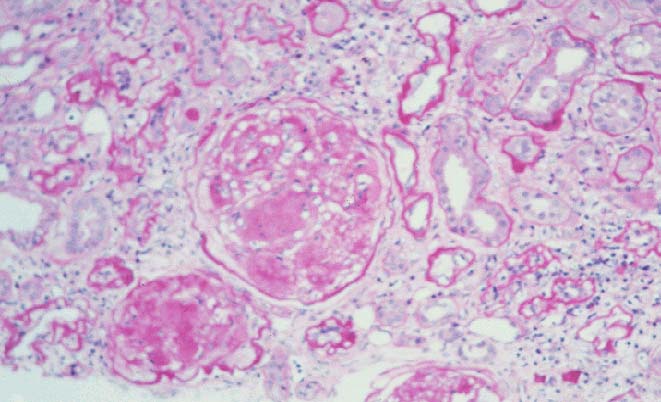

Overlap Fig A vs Fig B - Are these images from the same section? |

Fig A |

Fig B |